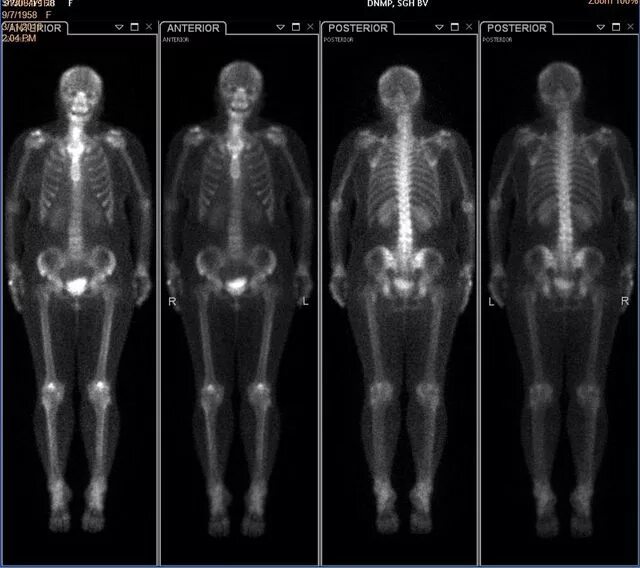

Метастазы скелета